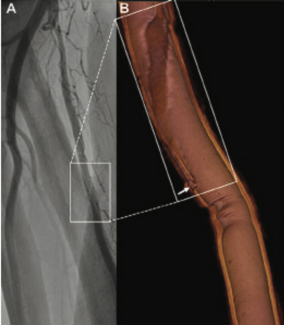

A 75-year-old man underwent right transradial coronary angiography because of acute myocardial infarction. Postprocedural radial angiography revealed a dissection with a spiral luminal filling defect in the proximal radial artery,...